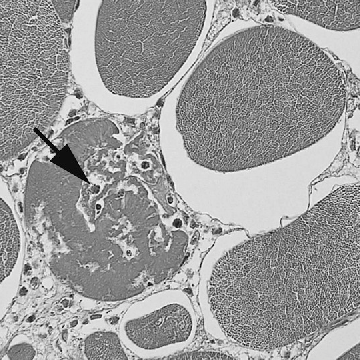

Broiler chickens have well-developed muscle tissue for meat production. Recently, inflammatory changes in the breast muscle of broilers have been increasingly reported (Kuttappan 2013, Hosotani 2020). However, the pathogenesis of these lesions still remains unclear. We focused on the relationship between skeletal muscle myoblasts and inflammatory responses.

Fig 1. 肉用鶏の筋組織における炎症 / Inflammation in broiler muscle tissue

(Kawasaki 2016)